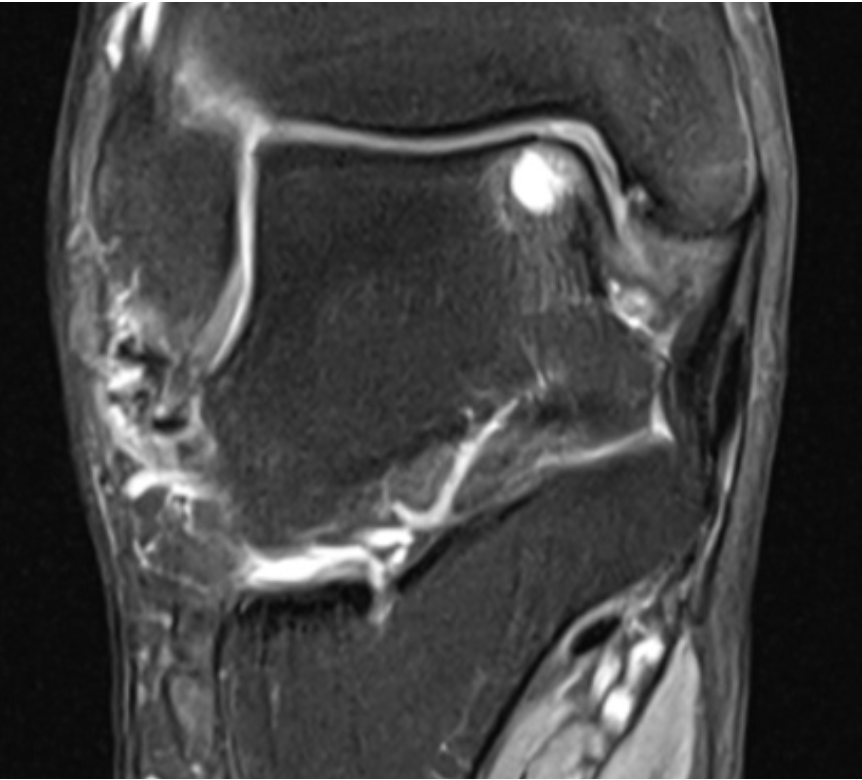

What is Talus OCD Oats Surgery?

- The surgery involves taking bone and cartilage from the outside of the knee joint that is not used often and transferring it to the defect in the talus.

- This often requires cutting the tibia bone for access to the talus; this is then fixed back to the original position after the surgery.